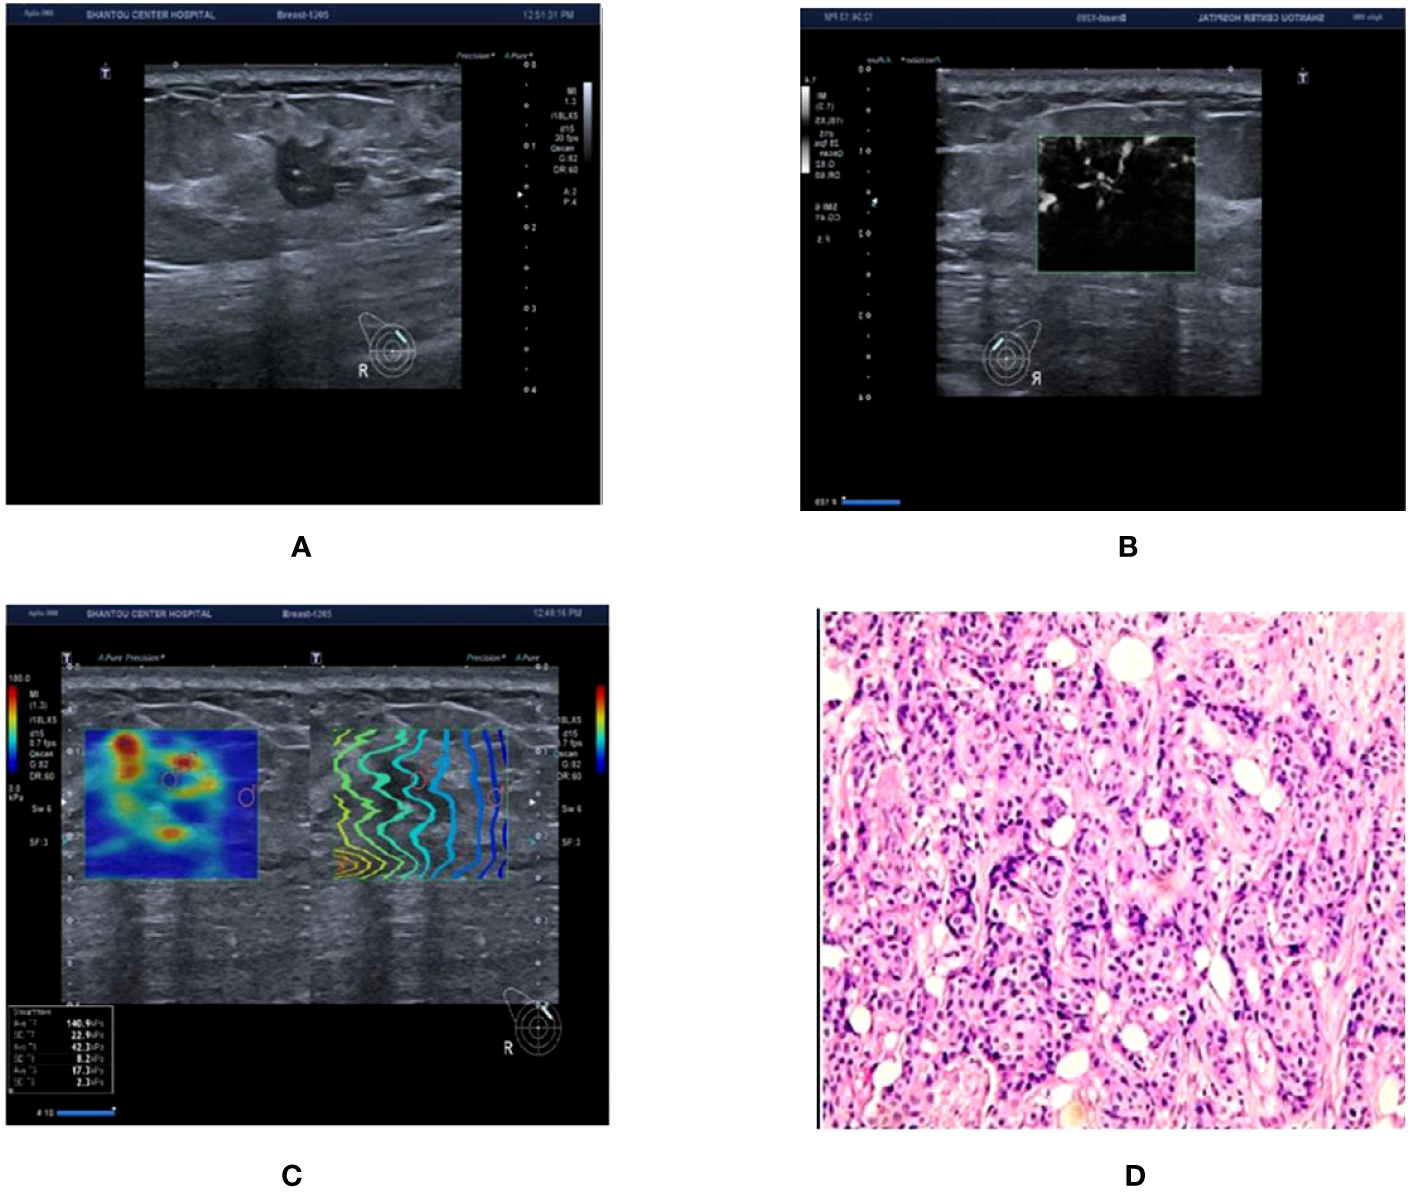

Figure 3

Ultrasound and pathological graphs: A 50-year-old female patient with a right breast nodule received ultrasound and pathological biopsy examinations. (A) An irregularly shaped, crab-like hypoechoic nodule is detected in the upper outer quadrant of the right breast, with unclear boundaries, classified as BI-RADS 4c. (B) mSMI image demonstrates that the microvascular morphology is radicle-shaped, with an increased BI-RADS level of 1 classified as BI-RADS 5. (C) Shear wave elastography image: Emax is 140.9 kPa, which is higher than 77.25 kPa, resulting in an increase or no change in the BI-RADS classification. (D) The nodule is an invasive ductal carcinoma based on pathological results.